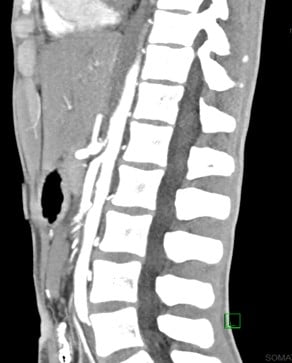

Abdominal computed tomography angiography during hospitalization

FINDINGS (abbreviated): Normal robust enhancement of abdominal aorta, origins of celiac, superior mesenteric and renal arteries are demonstrated. The aortomesenteric angle measures 14 degrees. The aortomesenteric distance at the level of the duodenal crossing is 6 mm.

IMPRESSION:

- Interval resolution of previously demonstrated marked distention of the stomach. Proximal duodenum is mildly dilated, but significantly improved compared to prior.

- Both the aortomesenteric angle and aortomesenteric distance are decreased, as may be seen with SMA syndrome. Clinical correlation and follow-up care are recommended.

- Left chest tube is present with small left pneumothorax.

- Subcutaneous air is present with soft tissues in the lower chest.

- Small amount of posterior pneumomediastinum is present.

- Mild splenomegaly is present. The spleen appears elongated and relatively thin transversely.